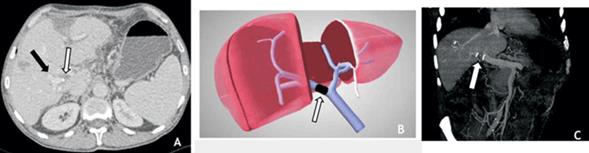

A las cinco semanas se evidenció por tomografía oclusión del origen de la vena porta derecha, la cual se encontraba repermeabilizada a nivel intrahepático (figura 2). El volumen hepático total (VHT) era de 1.408 cm3 y el volumen del FHR de 663,8 cm3, con un cociente FHR/ VHT de 47%, representando un crecimiento de 20% respecto al volumen inicial, por lo que a las siete semanas de la primera hepatectomía se procedió a la hepatectomía derecha. Se realizó ecografía intraoperatoria confirmando la oclusión del origen de la vena porta derecha, con repermeabilización intrahepática de ésta (figura 3). Se completó la cirugía propuesta sin incidentes. Buena evolución posoperatoria, sin elementos de FHPO.

Figura 2: A) Tomografía computada en fase portal realizada después de cinco semanas de oclusión de la vena porta derecha. Se observa el defecto de relleno de la rama derecha evidenciando el sitio de la ligadura (flecha blanca) con repermeabilización de las ramas intrahepáticas. B) Esquema de ligadura portal derecha (flecha blanca). C) Reconstrucción coronal MIP donde se observa la vena porta común y a nivel de la rama derecha los clips metálicos en el sitio de la ligadura, evidenciando el defecto de relleno vinculado al clipado de la misma (flecha blanca) y posterior repermeabilización.